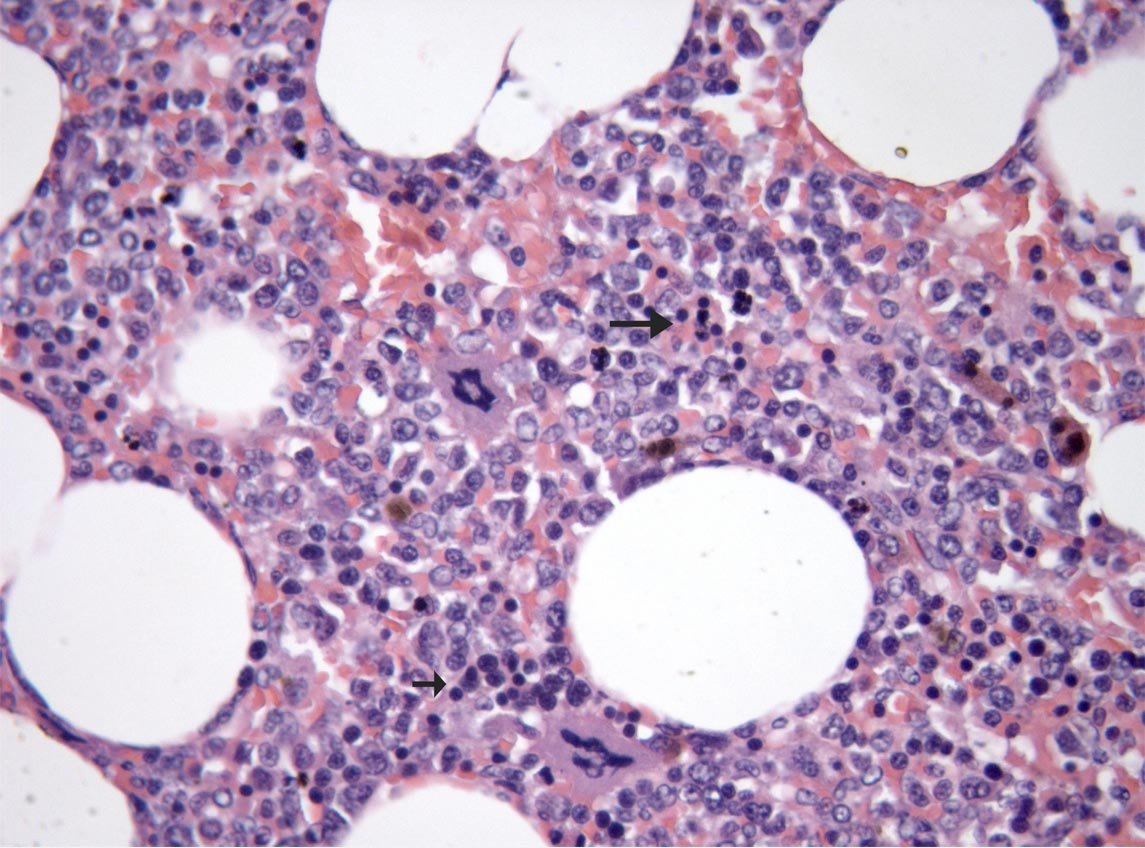

Fig.4 A bajo aumento se aprecian las vacuolas vacías( adipocitos) y el componente mieloide. A la derecha, fig. 5, las flechas señalan varios megacariocitos.

Fig. 6. Las flechas indican varios centros de hematopoyesis extra medular.